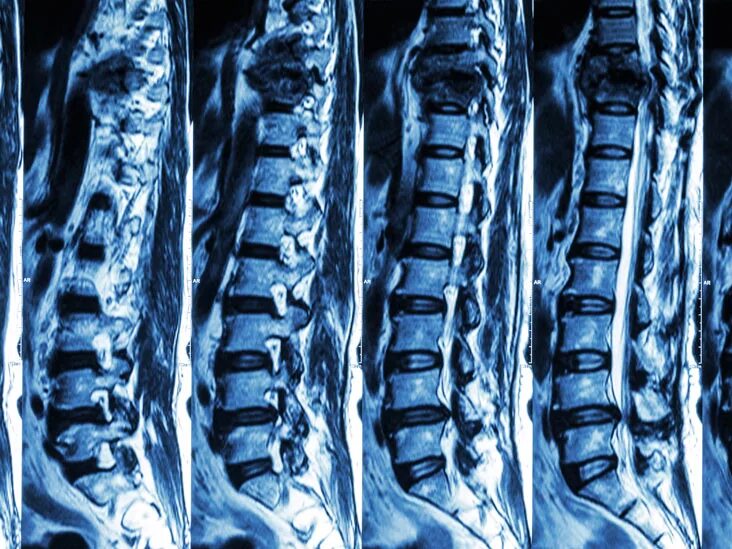

Как делают кт пояснично крестцового отдела